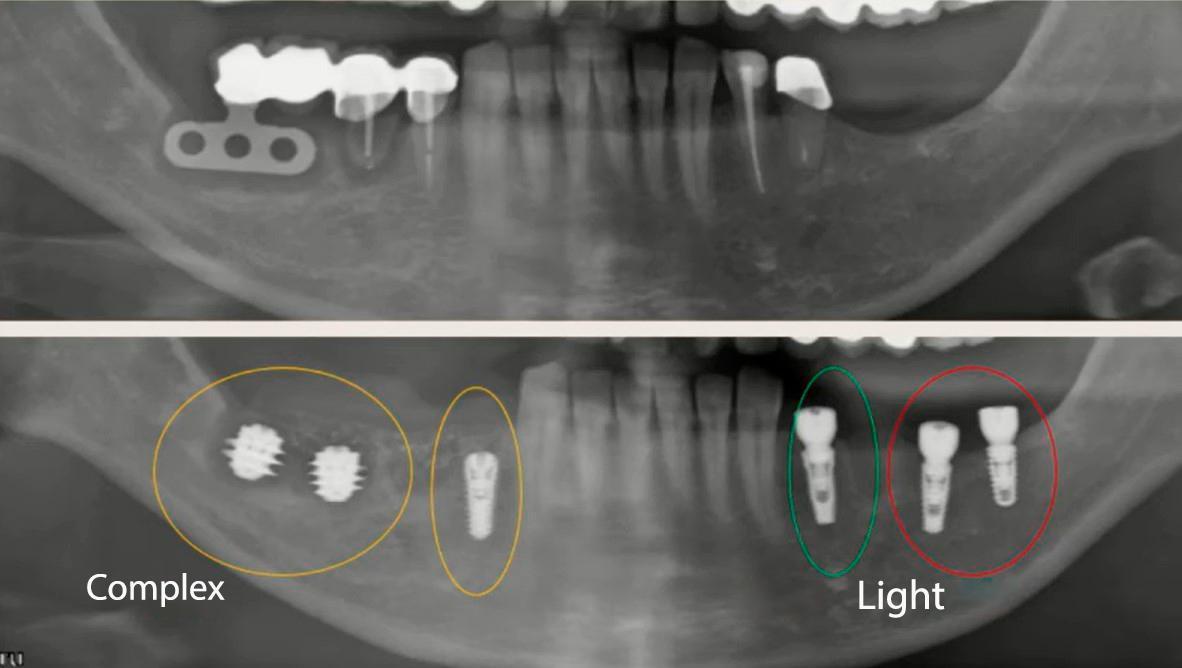

Before we discuss the study’s design and results, let’s briefly review the range of multi-unit abutments available for Full Arch-on-4/6 restorations. XGate Dental has developed three types of multi-unit abutments designed for immediate loading protocols like Full Arch-on-4/6:

The implant architecture in the model was complex, including three fences (support ribs) to simulate real structural elements at the bone-implant interface.

The researchers created a 3D model of the implant in CATIA and performed the simulation in ANSYS:

- implant length:8 mm

- diameter:4.5 mm

- three “fences”: two 2 mm, one 1.5 mm

- bone: 1 mm cortical layer + trabecular bone

- 81,000 nodes, 27,000 mesh elements